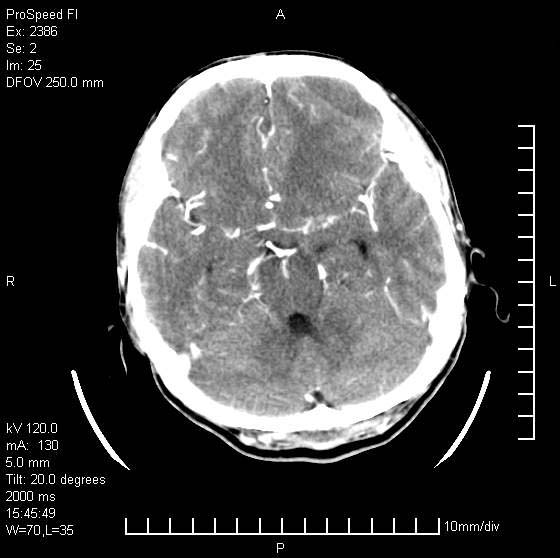

以下是引用天南地北在2007-9-19 18:43:00的发言:[br]典型慢性硬膜外血肿[br][br][本贴已被 天南地北 于 2007-9-19 18:44:11 修改过]

以下是引用曼一拍在2007-9-20 11:06:00的发言:[br]支持慢性硬膜下血肿.[br]慢性硬膜下积液:血肿有包膜,ct值稍高于脑脊液,增强可有染色。不典型者血肿可多呈梭形.是硬脑膜与蛛网膜之间的潜在腔隙内的血肿。[br]鉴别:[br]1\\硬膜外血肿:是颅脑外伤后脑膜或板障内血管破裂,血液在颅骨与硬膜之间积聚所致.通常是脑膜动脉破裂,也可因静脉窦破裂或颅骨的板障静脉出血,发生于外伤的着力部,常与颅骨骨折并存。脑膜动脉出血则急,若是板障静脉出血在则可有慢性。[br]2\\硬膜下积液:(硬膜下水瘤)[br]是由于蛛网膜破裂,脑脊液经蛛网膜破口进入硬膜下腔不能回流。或水肿阻塞而形成。[br]ct表现:颅骨内板下方新月形低密度区近似脑脊液密度;占位效应清,周围无脑水肿。[br]